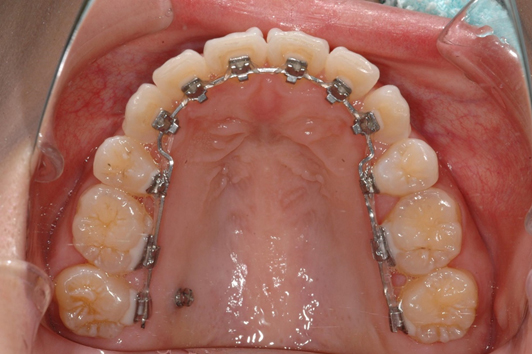

日本人の歯の色に合わせたブラケットとホワイトワイヤー

装置が見えない裏側矯正と矯正用インプラント